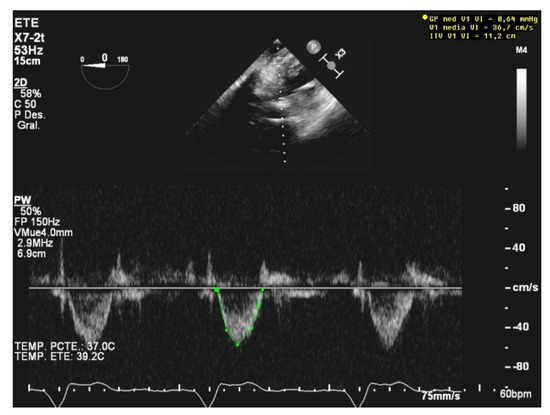

Echocardiographic assessment has a limited role in Impella-assisted patients because of the difficulty in measuring the common Doppler parameters due to the noise generated by the device and its placement at the left-ventricle outflow tract [38]. Nevertheless, readiness to wean can be assessed as a function of some imaging features such as a left-ventricular ejection fraction higher than 25%, an aortic velocity time integral higher than 12 cm/s, or a lateral mitral annulus velocity superior to 6 cm/s [39] (Figure 5).

Figure 5.

Impella device acoustic noise.

TEE is commonly used to assist placement, to guide management, and to reveal mechanical complications, as well as to assess the systolic function and concomitant valvulopathies and their severity [40,41].